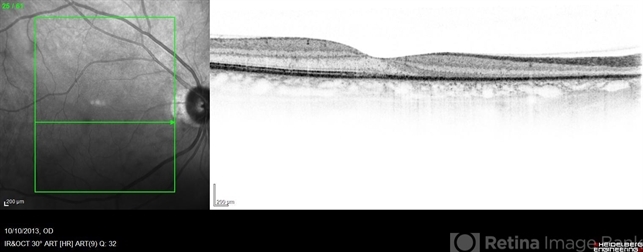

By Robert T. Wendel, MD

Retinal Consultants Medical Group - Uploaded on Oct 11, 2013.

- acute zonal occult outer retinopathy (AZOOR)

- Acute zonal occult outer retinopathy (AZOOR).